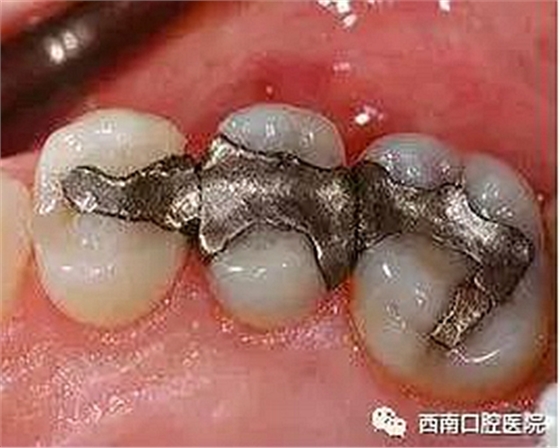

清潔干凈齲洞之后,然后醫(yī)生會用專用的充填材料進行充填,以恢復牙齒原來的形狀和大小。通常使用的充填材料有銀汞合金、復合樹脂材料、金或瓷等。

我們來看下各個材料充填之后的顏值吧!

銀汞合金(由銀、錫、汞和其他化合物組成)在牙科安全使用已近150年。但由于其材料長期使用后會有有害成分游離,對身體造成影響,現(xiàn)已逐步被時代舍棄了。